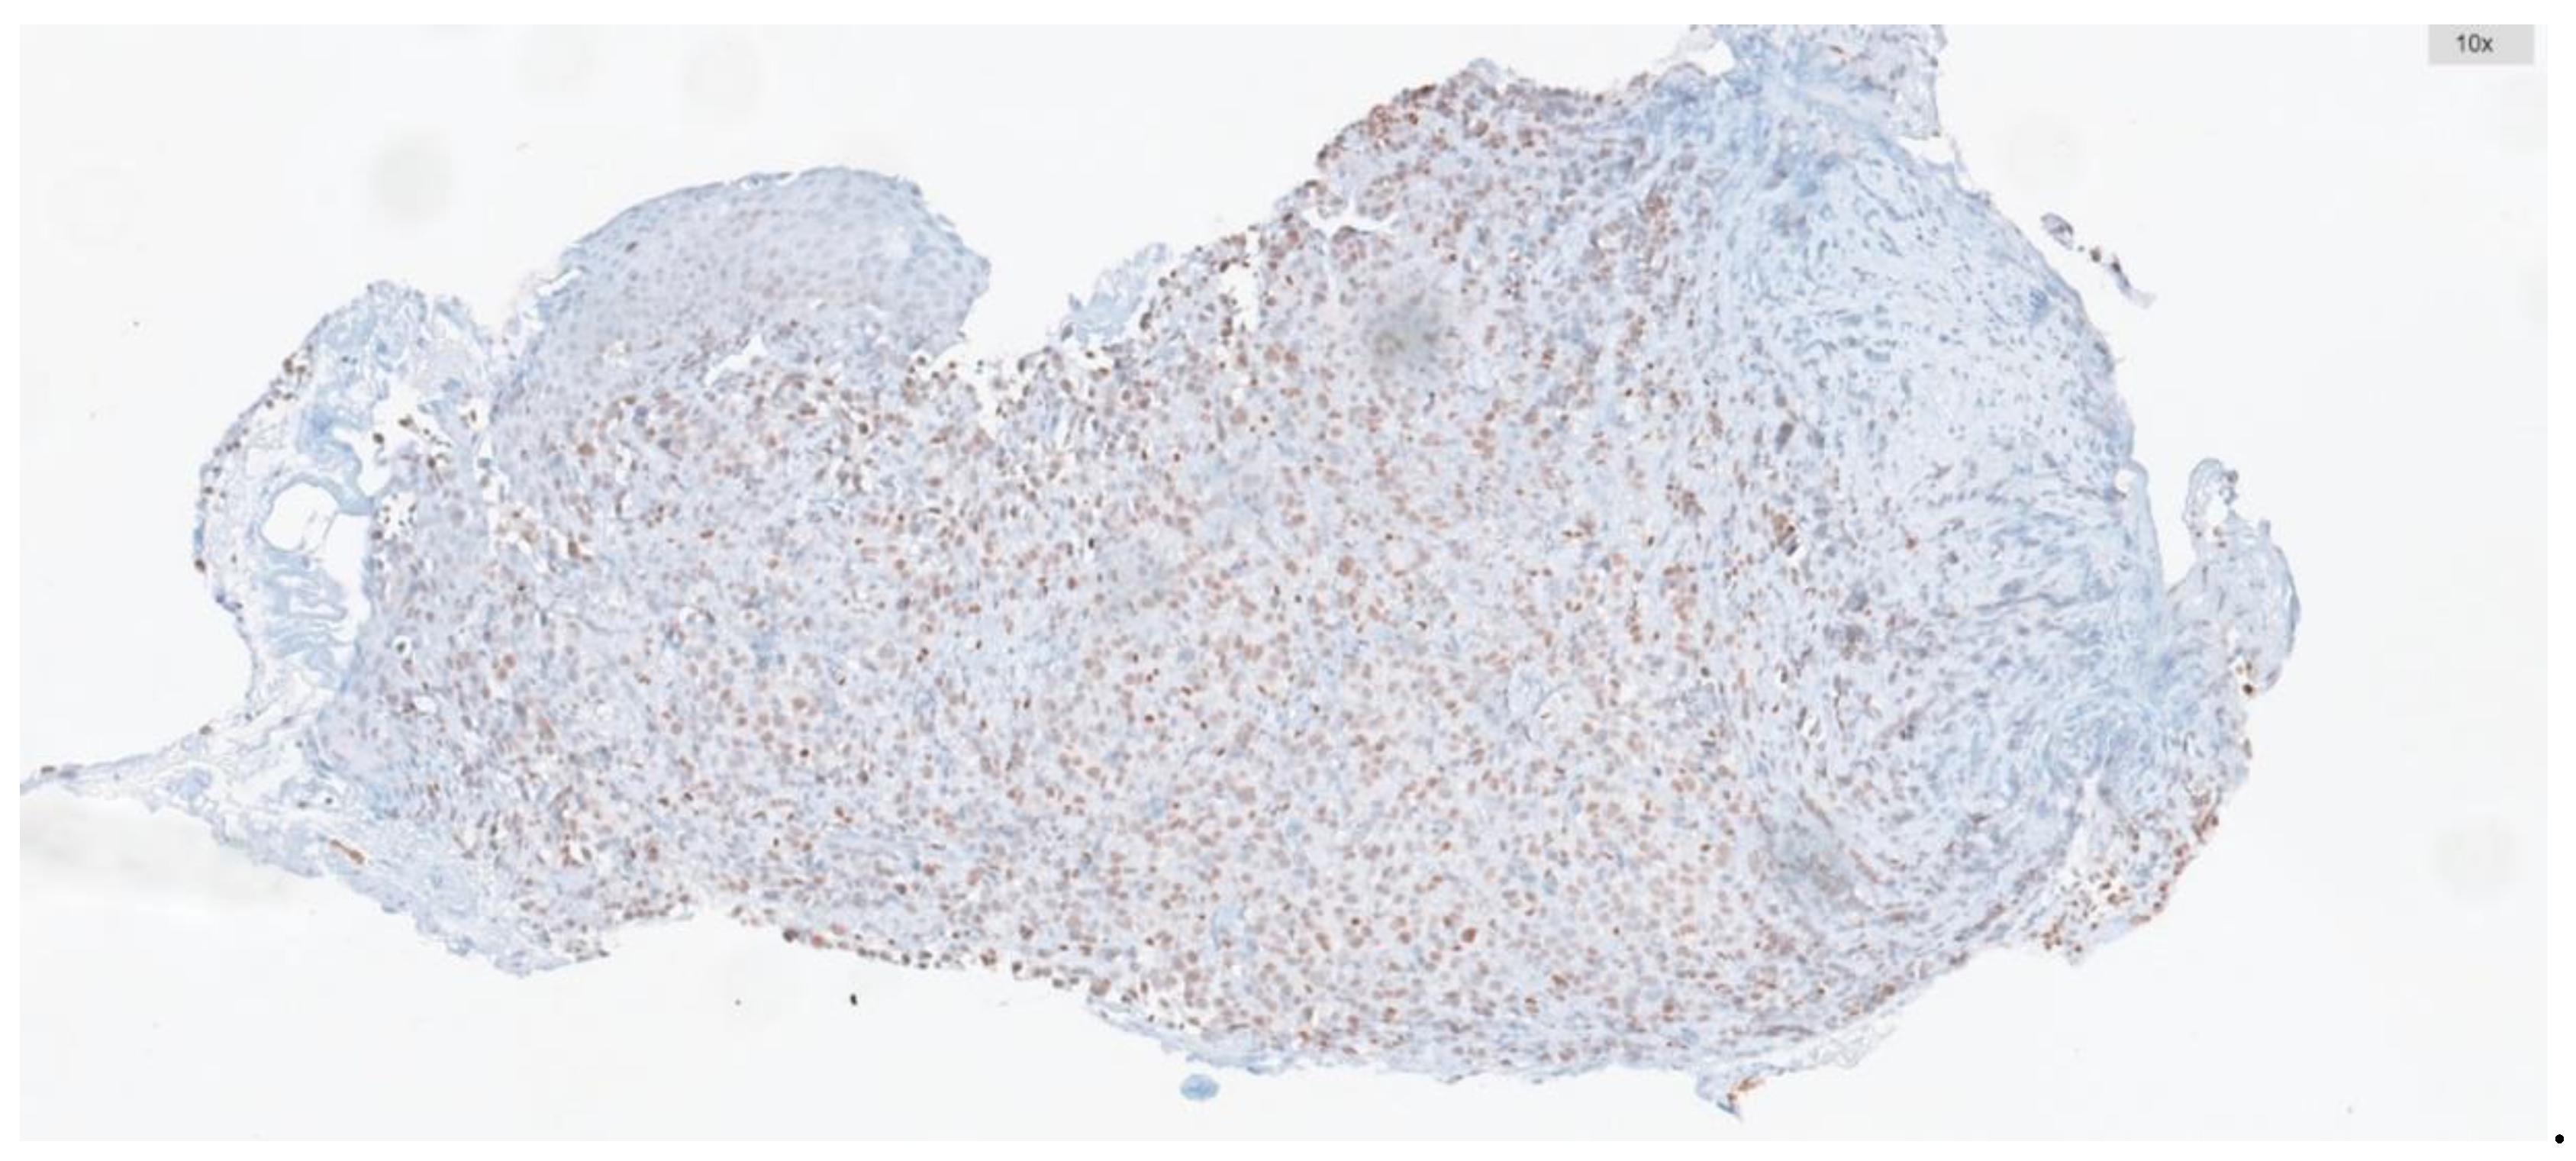

- Villaruz LC, Jones H, Dacic S, Abberbock S, Kurland BF, Stabile LP, et al. ATM protein is deficient in over 40% of lung adenocarcinomas. Oncotarget. 2016; 7:57714–57725. [CrossRef]

- Petersen LF, Klimowicz AC, Otsuka S, Elegbede AA, Petrillo SK, Williamson T, et al. Loss of tumour-specific ATM protein expression is an independent prognostic factor in early resected NSCLC. Oncotarget. 2017 Jun 13;8(24):38326-38336. [CrossRef]